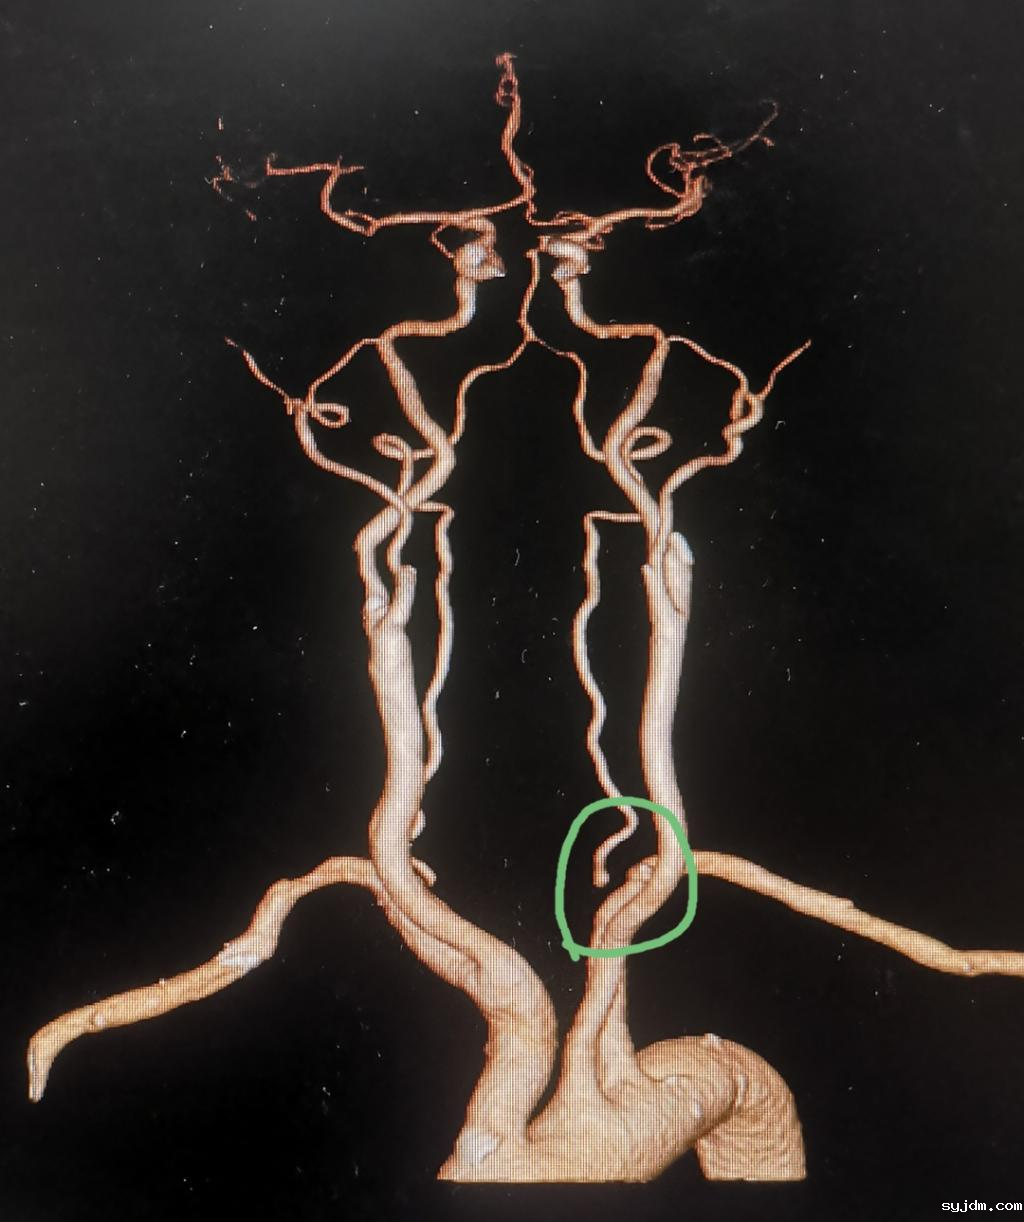

朱嗲嗲的双侧椎动脉起始部狭窄非常明显

血管像断了一截一样